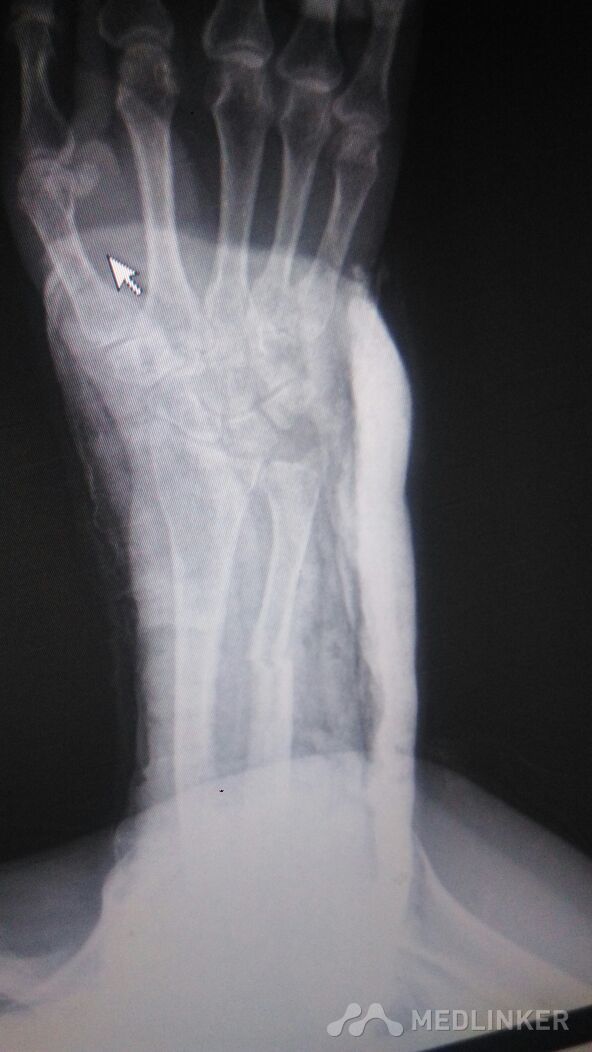

左侧尺骨骨折的治疗。

骨折 尺骨骨折

左前臂尺骨骨折,给行保守治疗。

不复位吧,差一点,复位吧!担心复位过度,不如不复位。还是尽一把力吧!